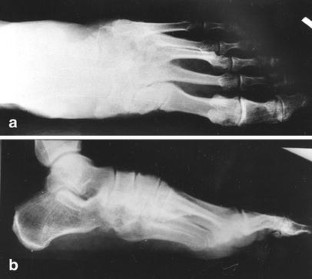

We report an unusual case of concomitant plantar tarsometatarsal (Lisfranc) and 1st and 2nd metatarsophalangeal (MTP) joint dislocations and fracture of the neck of the third metatarsal bone which has never been reported before. The plantar dislocation of the Lisfranc joint was treated by open reduction and fixation with K-wires; the dislocations of the MTP joints and neck fracture of the third metatarsal bone were treated by closed reduction and percutaneous fixation with K-wires and immobilized with a plaster cast. At the 5 year follow-up examination, our patient had no complaints, but the radiograph showed degenerative changes of the Lisfranc and the 1st MTP joint.

Fig. 1a,b.